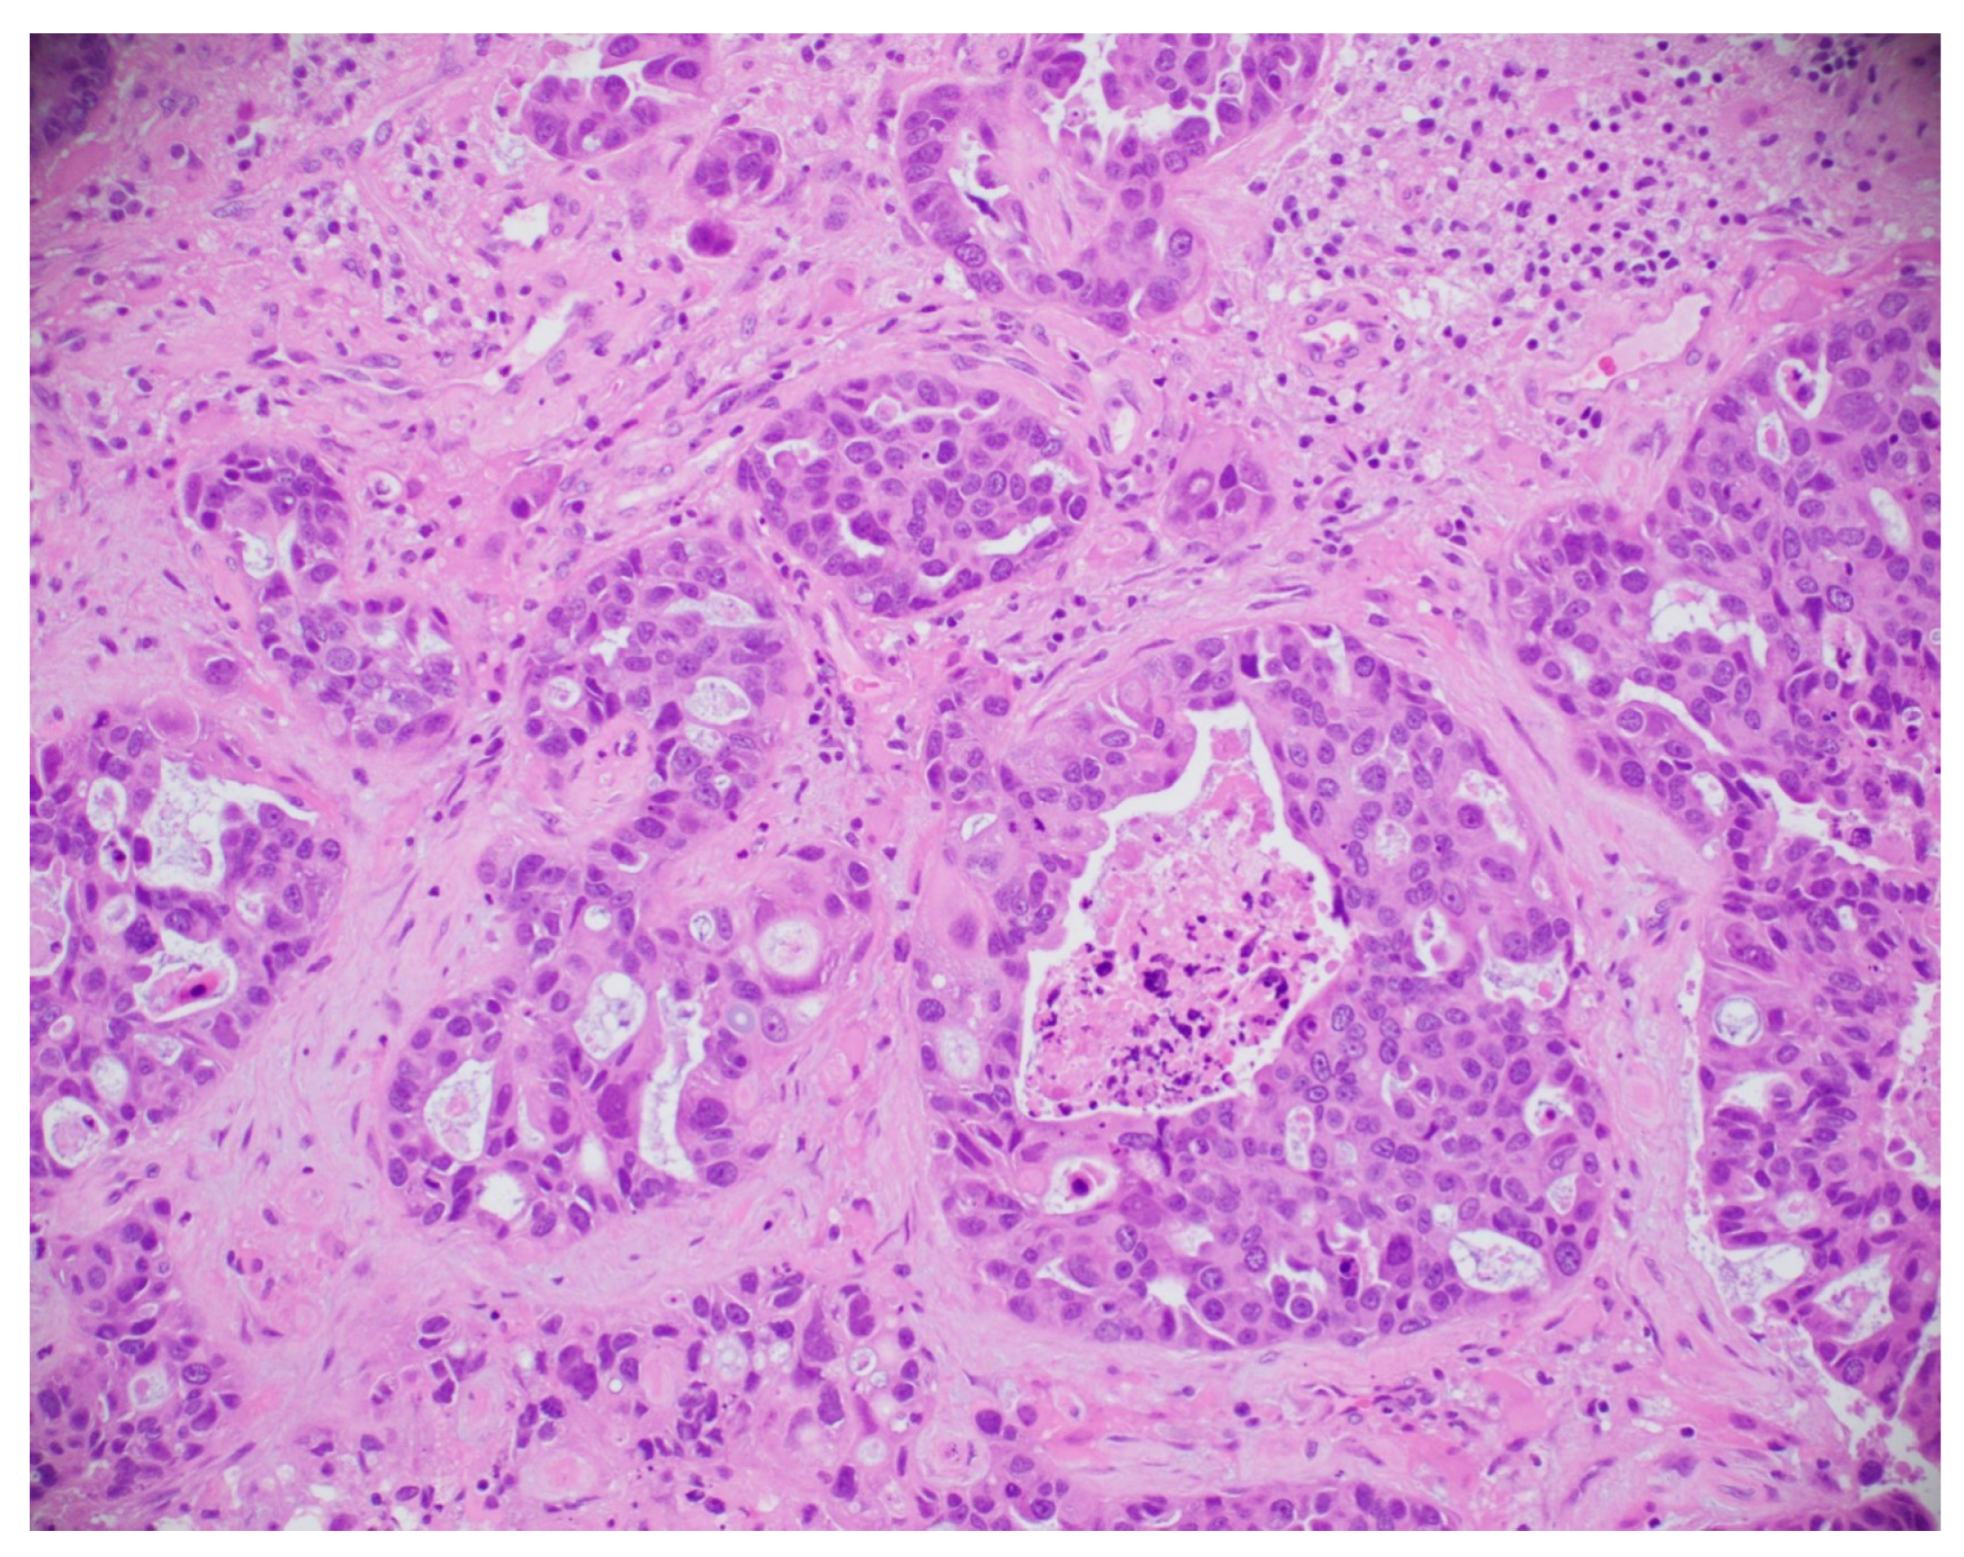

8.5. Histopathological Image-Based Breast Cancer Detection

This subsection explores the application of histopathological and microscopic imaging, key diagnostic tools for BC detection that involve examining tissue samples at the cellular level to identify malignancies and support accurate diagnosis and treatment planning. A simple histopathological image is shown in Figure 21.

Figure 21.

A sample histopathological image [135].